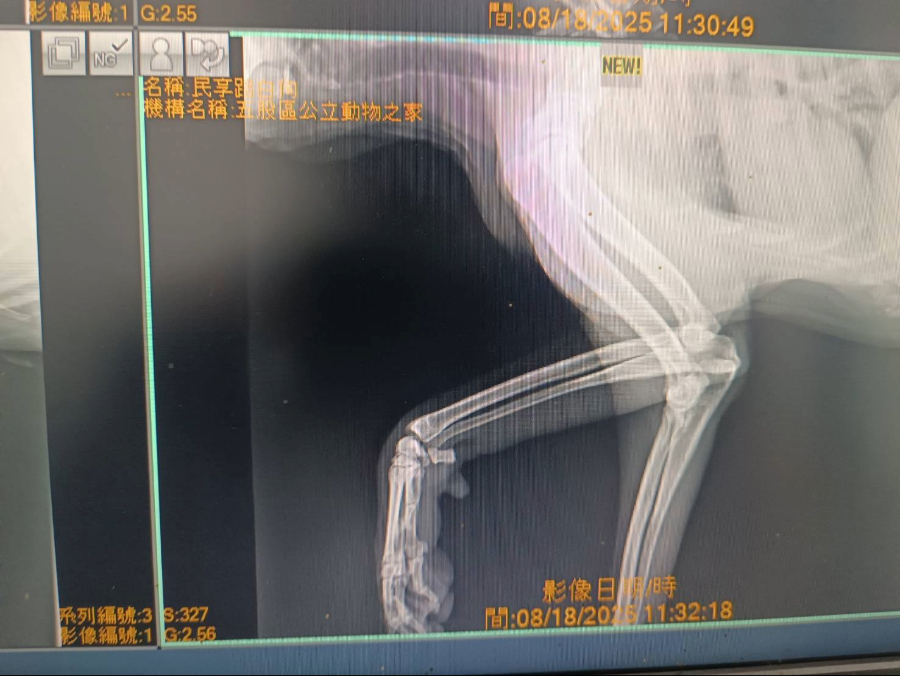

在接獲民眾通報後,動保處人員立即趕赴現場,發現大黃弟的前腳潰爛嚴重、深可見骨,推測已疼痛多時,仍努力行走覓食,救援人員小心將牠送往五股動物之家,獸醫師立即進行清創、包紮、投藥及X光檢查,確認傷勢未波及骨頭,經過多日細心治療與營養補充,大黃弟的傷口逐漸癒合,體力與精神明顯恢復許多,原本緊張的行為也漸漸變得比較親近人,願意與人互動相信人類。 在大黃弟康復期間,住在林口竹林寺附近的一位老師主動表達願意認養,並多次前來動物之家為大黃弟加油打氣,老師早年旅居海外,在世界各地教書,能說五國語言,近年選擇回到台灣落葉歸根,持續奉獻教育,她表示,自己從大黃弟年輕時就常見牠在社區中活動,「牠一直很安靜、從不打擾人,看著牠變老、受傷又被救回,真的讓我很感動。」她說,或許是因為多年在外見過不同的風景,也更能體會穩定與歸屬的可貴,「希望牠能在熟悉的地方安心生活,這份陪伴對我來說也很珍貴。」